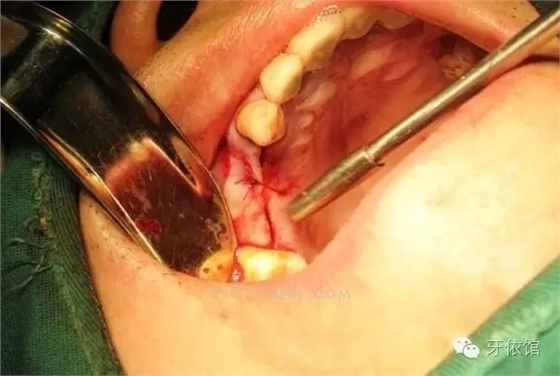

切開翻瓣

右上4,6牙位定位,先鋒鉆鉆至距離上頜竇底1-2mm處,改用CAS鉆穿透一個(gè)窩洞竇底。